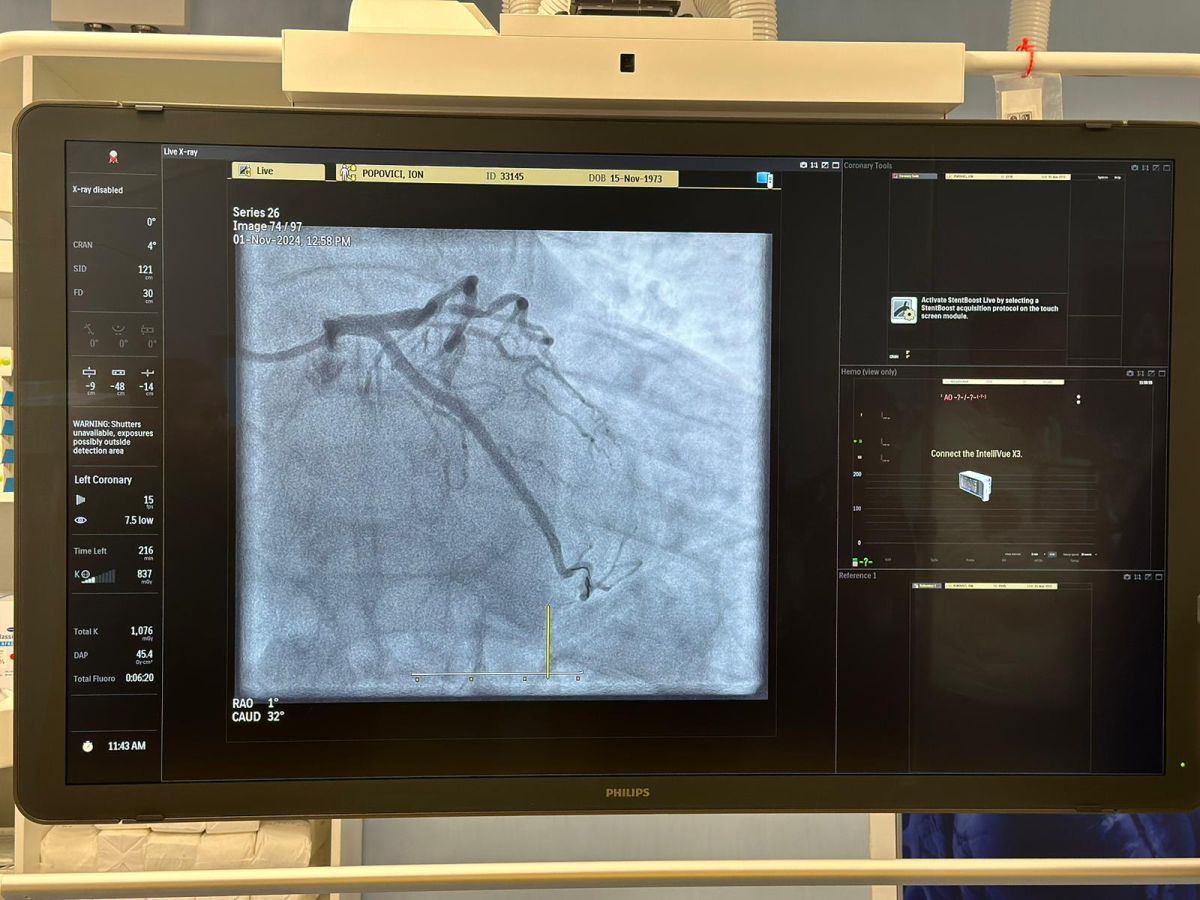

Mărturiile pacienților

Ion Popovici, un pacient în vârstă de 51 de ani din Târgu Jiu, a vorbit despre experiența sa la Spitalul Județean, după ce a beneficiat de intervenții în cadrul laboratorului de angiografie. „Totul a decurs impecabil. Am 51 de ani și m-am simțit rău; este adevărat, am o slujbă stresantă, dar nu m-am gândit niciodată că am grave probleme cu inima. Am intrat reticent în Spitalul Județean, dar am fost foarte mulțumit de tot. Am stat internat două zile după procedură și alte câteva zile înainte, căci nu eram bine deloc. Mi-au implantat domnii doctori două stenturi, angioplastie am făcut și toți s-au comportat impecabil. Am văzut cât se muncește în Secția Cardiologie, și le mulțumesc. Este un lucru foarte bun pentru gorjeni că avem angiograf aici; mie îmi spuseseră că vor să mă trimită la Craiova, dar apoi a venit echipa medicală aici și au făcut intervenția. Cu cât avem un spital mai dotat cu aparatură, cu medici buni, este bine pentru noi, pacienții care au nevoie de spital”.